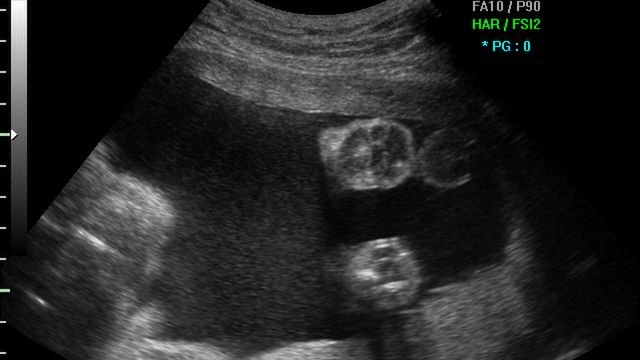

/ 5Płód w 26 tygodniu ciąży - układ nerwowy

Dzięki coraz lepiej wykształconemu układowi nerwowemu, dziecko wykonuje niektóre odruchy bezwarunkowe